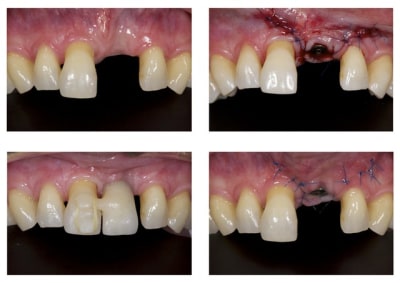

Comme demandé en MP voici le contrôle 10 mois après la pose.

C'est acceptable je pense. Ce traitement a ses limite bien sûr mais peut être une indication voire une alternative dans certains cas spécifiques comme celui-ci.

Au passage, qui connait le nom que l'on donne à cette collerette de GA que l'on voit sur 13-12-11-22-23, j'ai oublié.

Je ne sais pas si tu as réellement ingressé car quad je regarde ta radio du départ et celle que tu viens de mettre, ton apex arrive pratiquement au même niveau de spire, à savoir au niveau de la troisième spire en partant de l'apex de l'implant. Il y a quelque chose qui m'échappe.